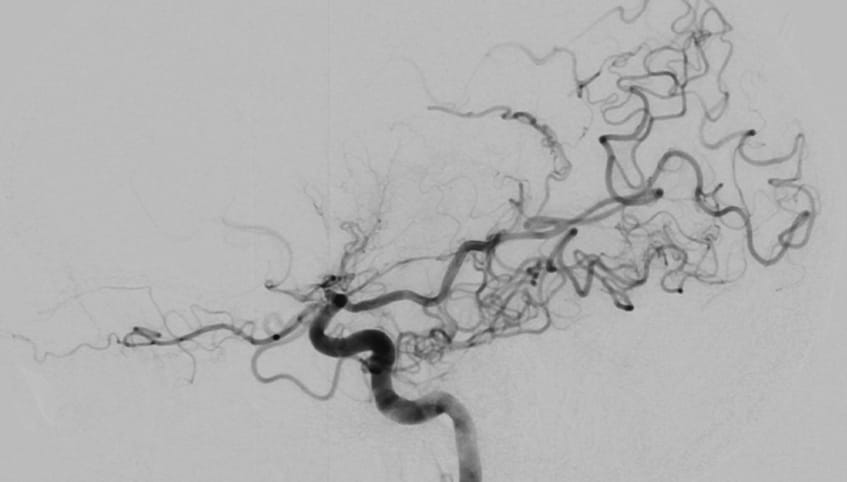

At the health system, specialists injected dye into Jason's brain to visualize the blood flow. The test, known as a cerebral angiogram, confirmed the moyamoya disease diagnosis. The carotid artery on the left side of Jason's brain was 98% blocked, the telltale cluster of small vessels clearly visible.

The walls of Jason's carotid artery had thickened, reducing blood flow to his brain. To compensate, tiny blood vessels opened at the base of his brain in an attempt to supply blood. However, the cluster of small vessels could not do the job of the major artery, and the lack of blood to his brain caused Jason's stroke.

Found all over the world, moyamoya disease – named for the “puff of smoke” the small blood vessels resemble – is most common in East Asian countries and among people of East Asian descent. To his knowledge, Jason doesn't have Asian ancestry, which makes his case even more unusual.